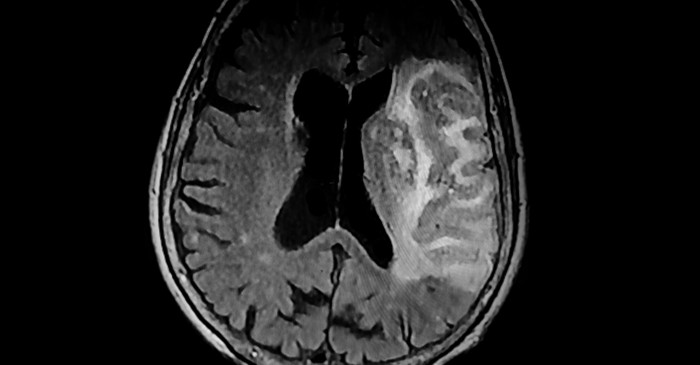

뇌출혈은 뇌 속 혈관이 터지면서 뇌조직 안에 피가 고이는 질환이다.

전체 뇌졸중 환자의 약 15%를 차지하지만, 사망률은 가장 높다. 문제는 증상이 갑자기 찾아오고, 단 몇 분 사이에 의식이 사라질 수도 있다는 점이다. 뇌출혈은 고혈압, 뇌동맥류 파열, 외상, 뇌혈관 기형 등 다양한 원인으로 발생한다. 혈관이 약해진 상태에서 혈압이 순간적으로 상승하거나, 뇌혈관 벽이 퇴행성 변화로 약해지면 쉽게 터질 수 있다. 고령층, 흡연자, 음주자, 고혈압 환자에게서 특히 위험이 높다. 최근에는 스트레스와 불규칙한 생활습관, 과도한 카페인 섭취도 위험 요인으로 지목되고 있다.

뇌출혈의 생존율은 출혈의 크기와 부위, 발견 시점에 따라 달라진다. 일반적으로 출혈량이 30㎖ 이상이면 예후가 좋지 않으며, 뇌간(숨뇌) 부위 출혈은 생명 유지 기능을 직접적으로 위협한다. 초기 대응이 무엇보다 중요하다. 증상이 의심되면 즉시 119에 연락하고, 환자를 눕힌 상태로 움직이지 않게 해야 한다. 머리를 약간 높게 유지해 뇌압 상승을 막는 것도 도움이 된다. 병원에서는 CT나 MRI를 통해 출혈 위치와 정도를 확인한 뒤, 수술이나 약물치료로 뇌압을 조절하고 추가 출혈을 막는다. 수술이 불가능한 경우라도 집중치료실에서 혈압 조절과 산소 공급, 체온 조절을 통해 생명을 유지할 수 있다.